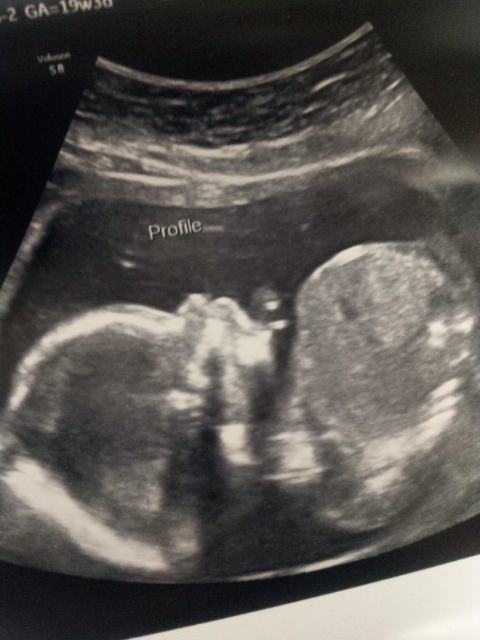

My u/s day went amazing. Being a FTM it was pretty much everything I expected. Baby was quite active and the tech said we had a tall baby on our hands! I posted a pic last week I do believe! Still team green!